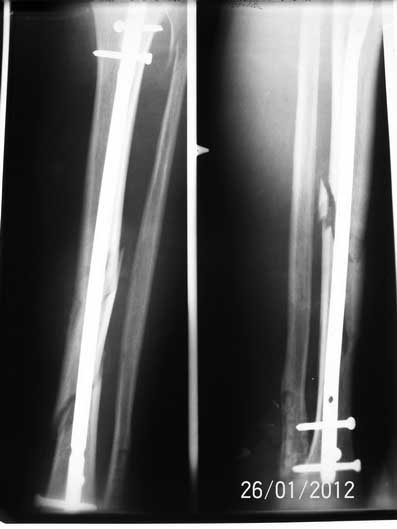

[Ortho] Фрагментарный перелом большеберцовой кости

Спасибо всем откликнувшимся! Докладываю результат. Свищ после удаления лигатуры за неделю затянулся. Фиксаторы с лодыжек удалены, БИОС. Мы удовлетворены, пациент доволен.

Имя     : 6.jpg